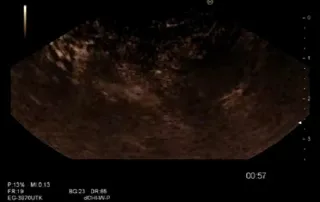

Endoscopic sumbucosal dissection (ESD)

ESD of a large polyp in the rectum involving [...]